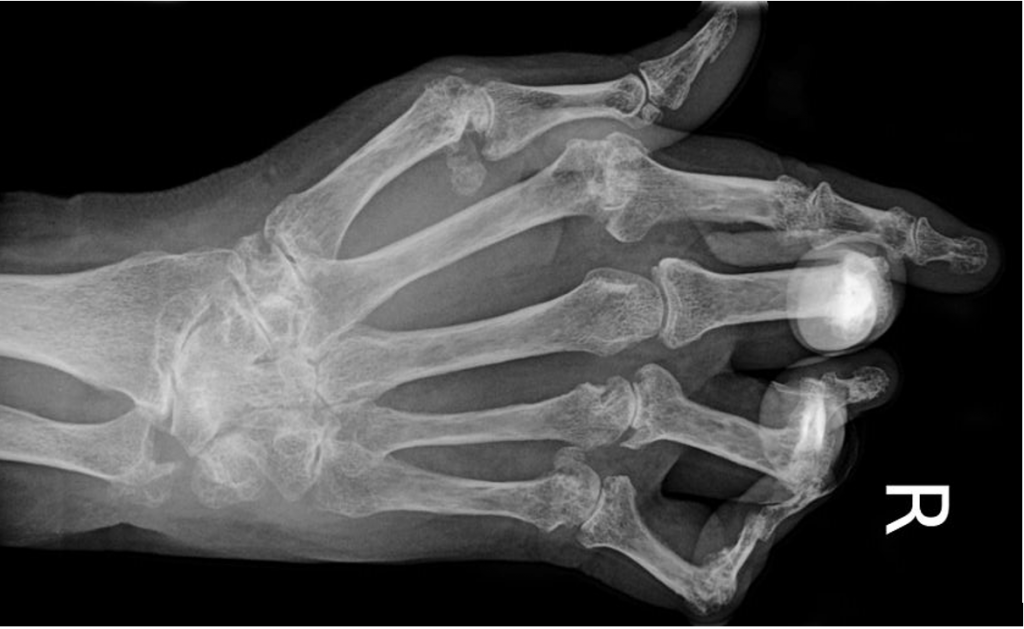

Research by the OSU College of Engineering’s Brian Bay and scientists from the Royal Veterinary College in London and University College London developed a sophisticated scanning technique to view the “loaded” joints of arthritic and healthy mice – loaded means under strain, such as an ankle, knee or elbow would be while running, walking, throwing, etc.

“With low-dose pink-beam synchrotron X-ray tomography, and mechanical loading with nanometric precision, we could simultaneously measure the structural organization and functional response of the tissues,” Bay said. “That means we can look at joints from the tissue layers down to the cellular level, with a large field of view and high resolution, without having to cut out samples.”

“Using intact bones and joints means all of the functional aspects of the complex tissue layering are preserved,” Bay said. “And the small size of the mouse bones leads to imaging that is on the scale of the cells that develop, maintain and repair the tissues.”